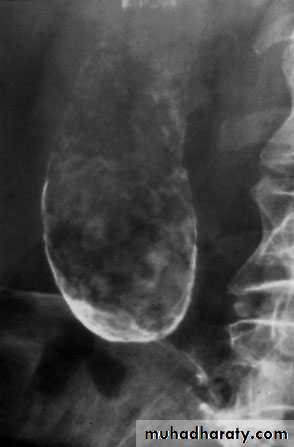

66Transhepatic cholangiogram showing a stricture of thecommon hepatic duct